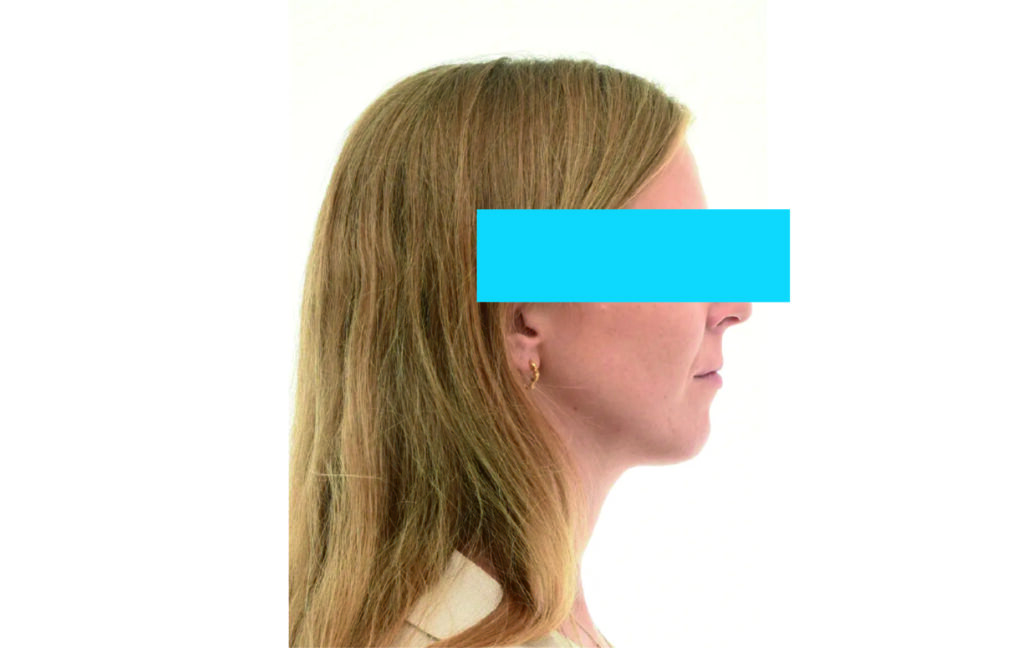

Soft Tissue Analysis: convex profile, lower third of the face increased, slightly retrusive upper and lower lips, lip strain on closure.